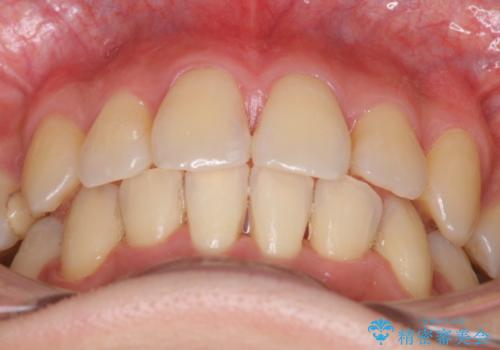

- 八重歯とガタガタを主訴に来院されました。

目立たないワイヤー矯正を希望されたので、上下左右のはを1本ずつ抜歯して、ハーフリンガル(上顎だけ裏側)にて矯正をすることにしました。